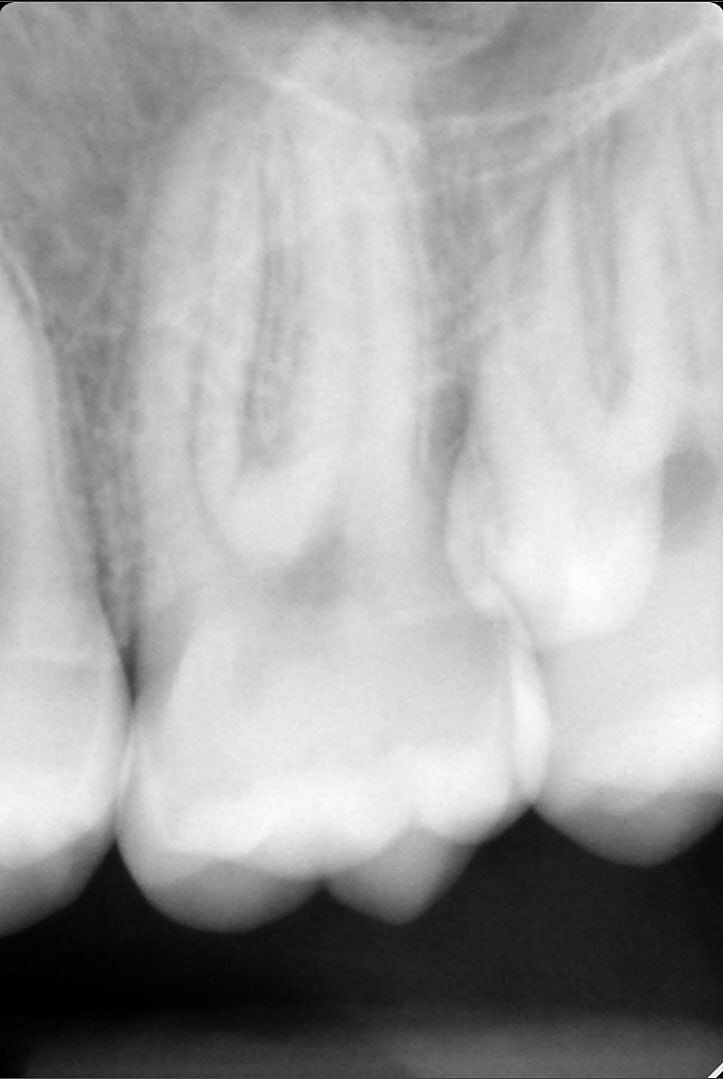

У дитини 14 років росте зайвий зуб. Біля верхньої шістки на піднебінні. Лікарі радять видаляти. Поділіться досвідом, хто видаляв, як пройшло і чи довго загоювалось?

вряд ли тут поможет чей-то опыт. снимок делали? у него полноценный корень? кривой или ровный?

фото

я не врач, но выглядит не очень, удаляйте. поболит пару дней, неприятно, но не смертельно. лучше так, чем потом он вам проблем наделает

Краще зробити КТ, а не рентген